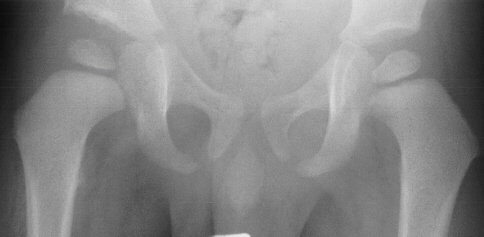

HISTORY: A 29 week old gestation male presented with bilateral knee dislocation, left hip subluxation, and right hip dislocation.

XRAYS: Reveal bilateral knee dislocations

,

and a left hip dislocation

.